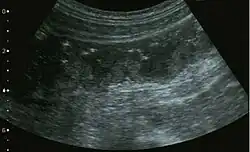

Im Ultraschall und in der Computertomographie kann man die langstreckige Darmwandverdickung des Dickdarmes erkennen. Endoskopisch sieht man im Dickdarm grünliche Fibrinbeläge, die teils fleckig, teils flächenhaft zu finden sind.